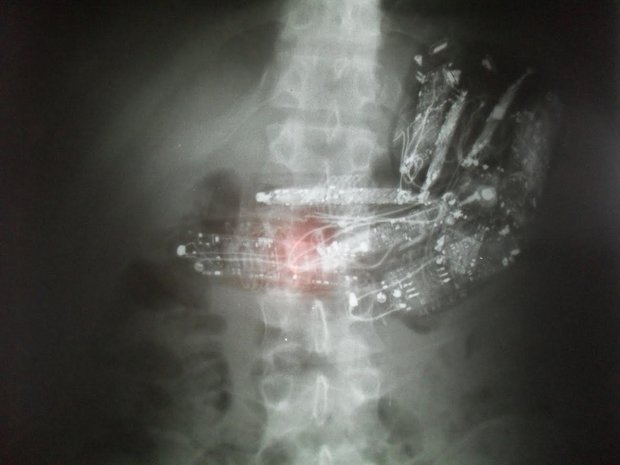

O terceiro detento estava com dez minicelulares conectados a fones de ouvido no estômago. Ele foi encaminhado para uma cirurgia para retirar os objetos. Ele segue internado se recuperando.

Um deles estava com 10 telefones dentro do estômago e precisou passar por uma cirurgia para retirar os aparelhos.